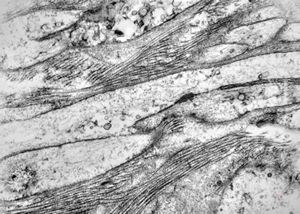

F, 39y. | collagenous and elastin fibers from corium

F, 39y. | collagenous and elastin fibers from corium

F,68y. | collagenous and elastin fibers from corium